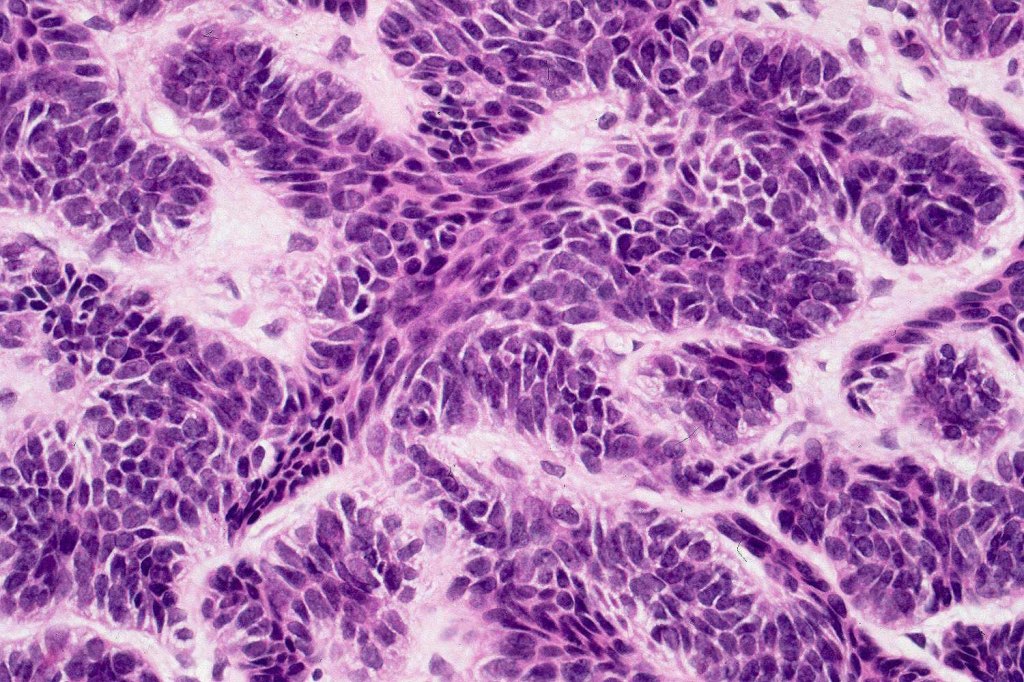

•The classical appearance consists of keratocysts & lobules of basaloid cells

•Basaloid lobules show peripheral palisading

•Retraction artifact and mucin deposition as seen in BCC are not present

•Mitoses & apoptosis may be present

•Perifollicular mesenchyme is always conspicuous and sometimes densely aggregated are seen indenting the baslaloid lobules (papillary mesenchymal bodies)

Trichoepithelioma should be distinguished from trichoblastoma since the latter is very rarely syndromic. Trichoepithelioma is largely a dermal tumor whereas trichoblastoma often extends from the dermis into subcutaneous fat or deeper in very large examples. Papillary mesenchymal bodies are much better formed and generally more obvious in trichoepithelioma. Trichoepithelioma must also be distinguished from basal cell carcinoma. Retraction artifact & stromal mucin are features of basal cell carcinoma and not trichoepithelioma. Papillary mesenchymal bodies are not seen in basal cell carcinoma.